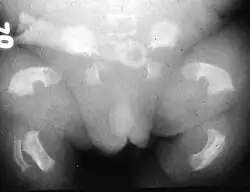

O Tipo 1 caracteriza-se por rizomelia extrema. A nível craniano, a base do occipital apresenta uma dimensão reduzida, incluindo o foramen magnum, testa proeminente e hipertelorismo ocular (afastamento amplificado das cavidades orbitais). No tórax ocorre platispondilia vertebral (achatamento dos corpos vertebrais) e as costelas apresentam encurtamento com extremidades metafisárias em forma de “chávena”, características que lhe conferem uma configuração mais estreita e em forma de triângulo. Na cintura pélvica, o ílion apresenta uma dimensão mais curta com a margem inferior horizontal, e o ísquion e a púbis possuem uma fisionomia mais larga e curta. Os membros superiores e inferiores caracterizam-se por ossos longos arqueados com diminuição muito significativa do comprimento e com metáfises alargadas. O fémur destaca-se pela sua aparência semelhante a um “auscultador de telefone”. Os membros superiores por vezes podem apresentam dígitos encurtados, verificando-se por vezes sinostose rádio-cubital.[4][6]